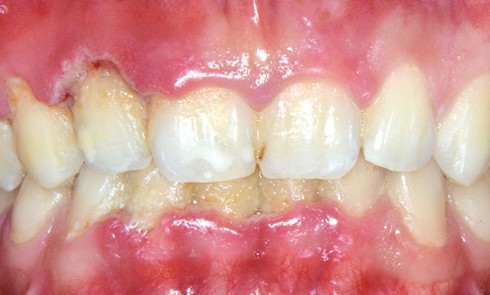

Article réservé à nos abonnés Les maladies parodontales ulcéronécrotiques

Les maladies parodontales ulcéronécrotiques sont des entités cliniques dont l’ulcération par nécrose de la gencive est le principal signe pathognomonique....